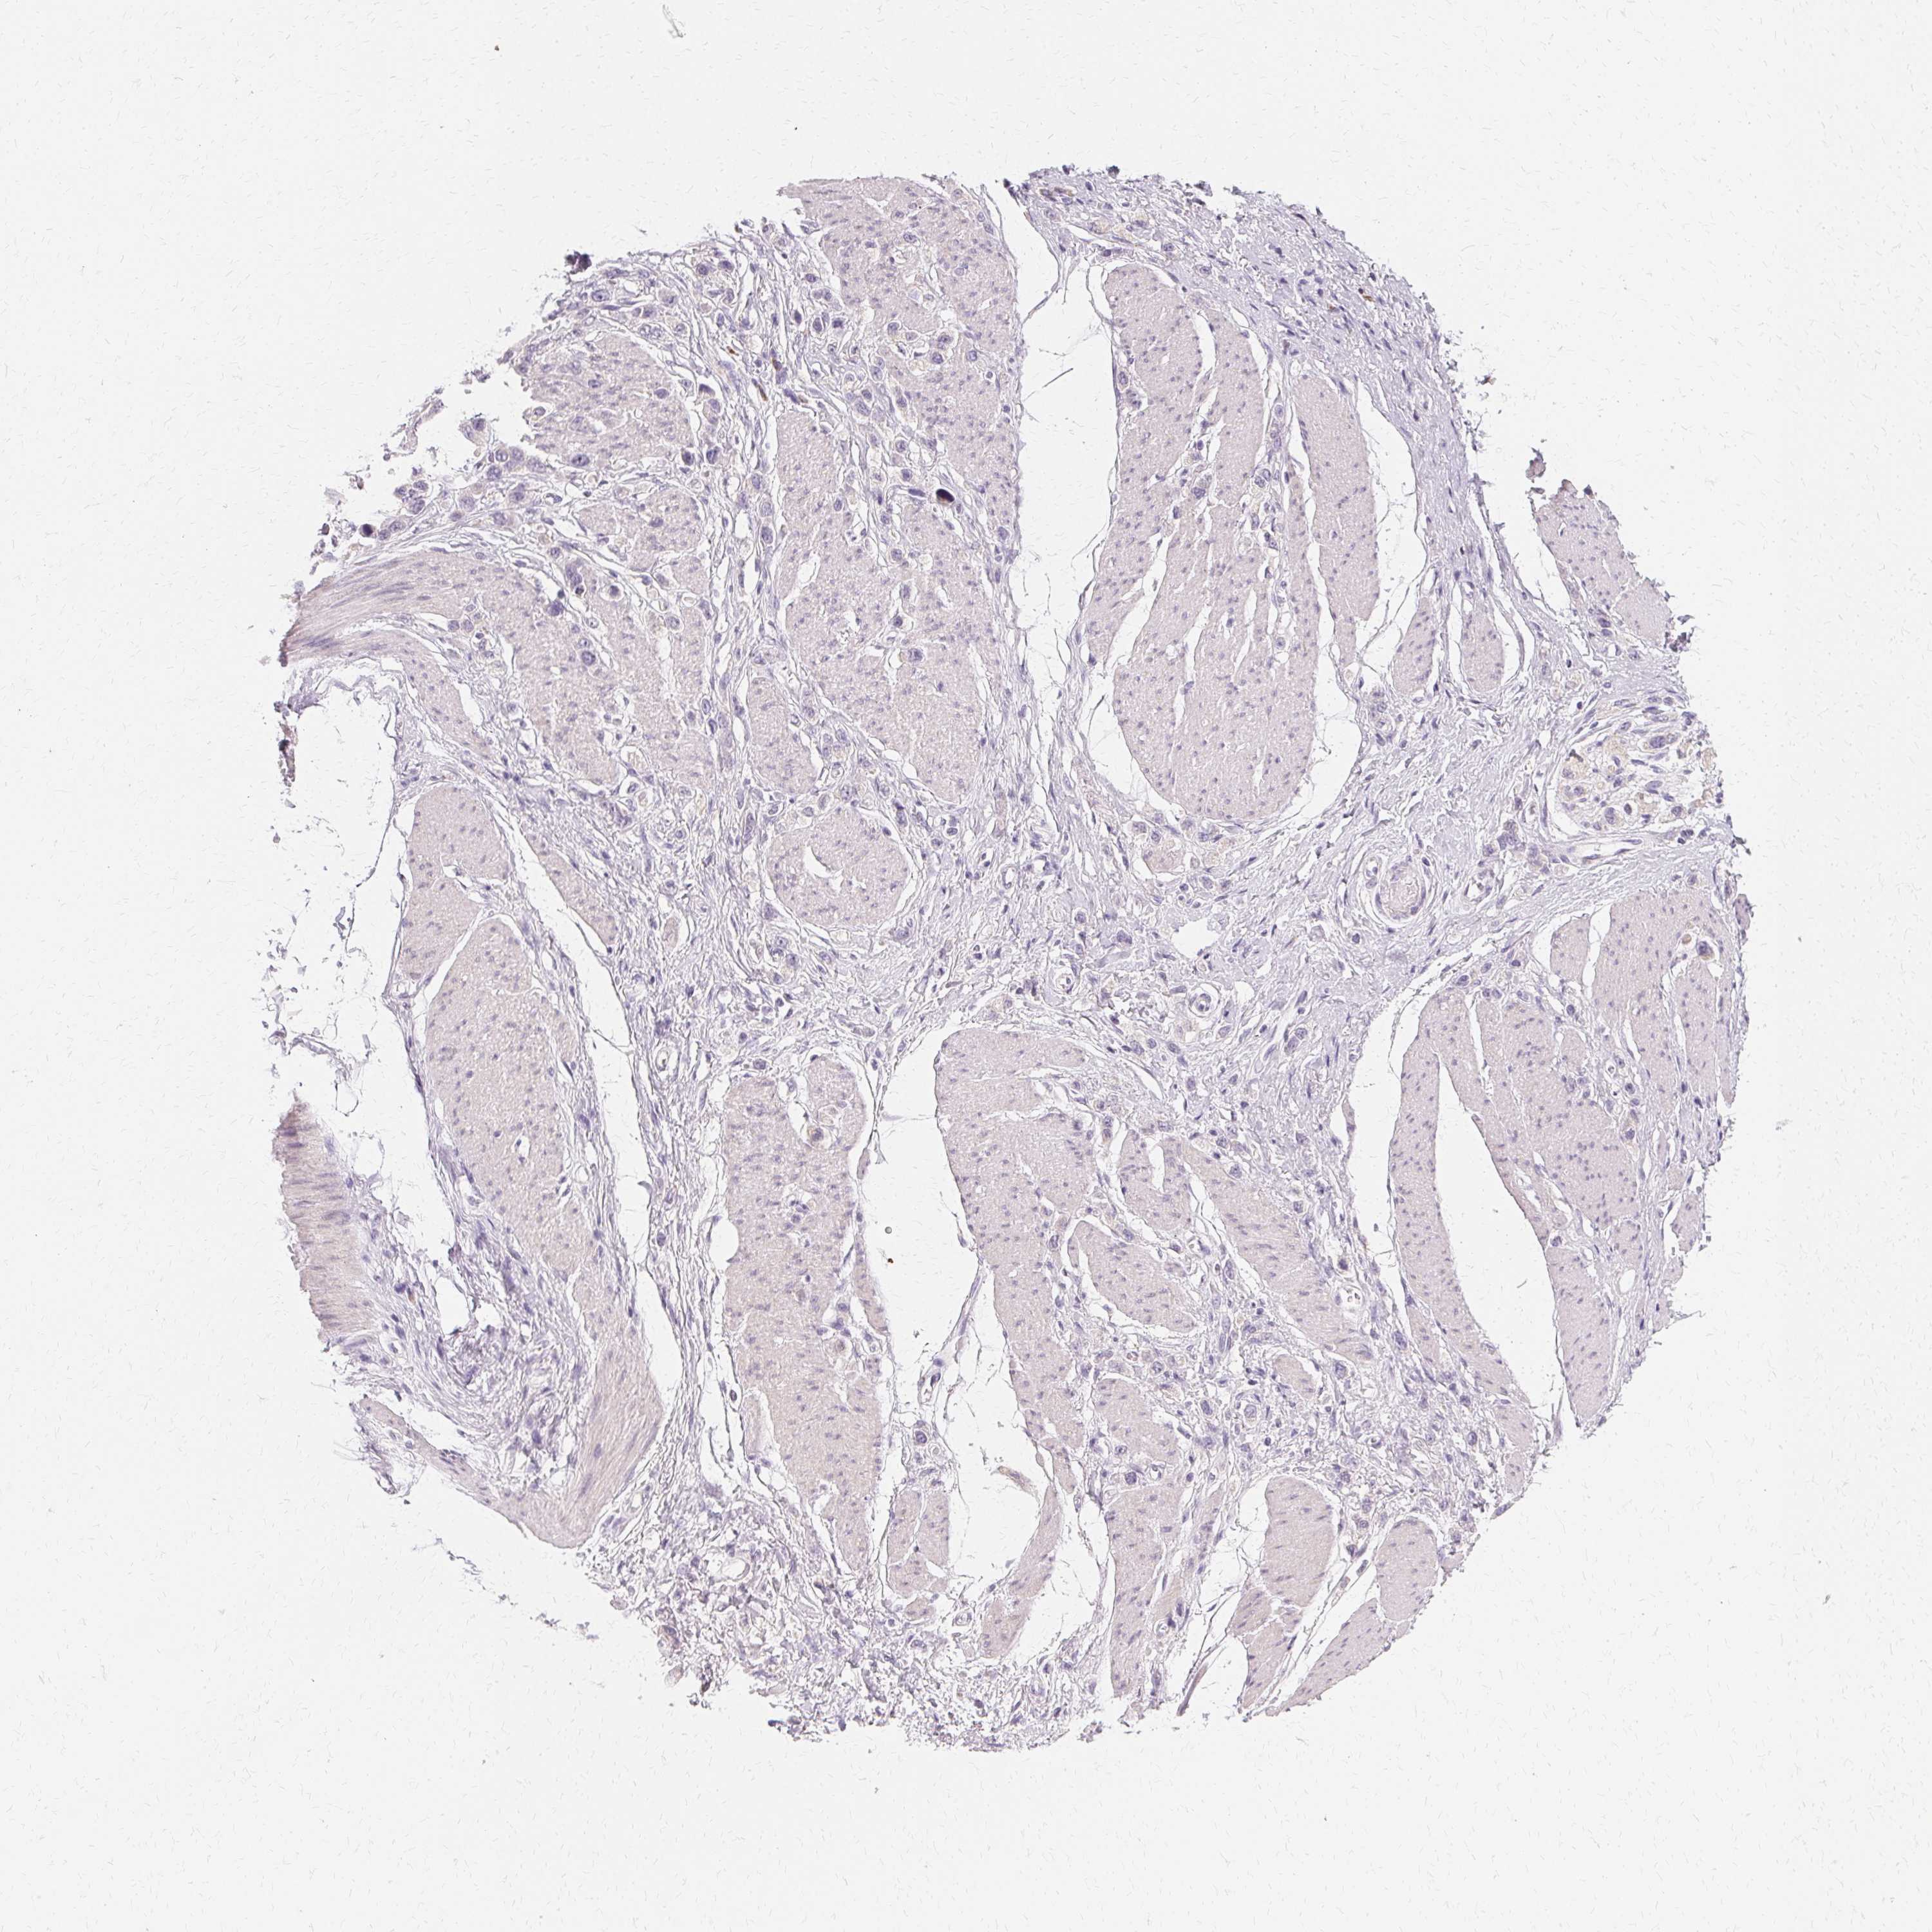

STOMACH CANCER - Protein expressioni

A mouse-over function shows sample information and annotation data. Click on an image to view it in a full screen mode. Samples can be filtered based on level of antibody staining by selecting one or several of the following categories: high, medium, low and not detected. The assay and annotation is described here.

Antibody stainingi

Antibody staining in the annotated cell types in the current human tissue is reported as not detected, low, medium, or high, based on conventional immunohistochemistry profiling in selected tissues. This score is based on the combination of the staining intensity and fraction of stained cells.

Each image is clickable and will lead to virtual microscopy that enables deeper exploration of all samples and also displays staining intensity scores, fraction scores and subcellular localization as well as patient and tissue information for each sample.

Antibody HPA048022

Staining

High

Medium

Low

Not detected

Intensity

Strong

Moderate

Weak

Negative

Quantity

>75%

75%-25%

<25%

None

Location

Nuclear

Cytoplasmic/membranous

Cytoplasmic/membranous,nuclear

Adenocarcinoma, NOS